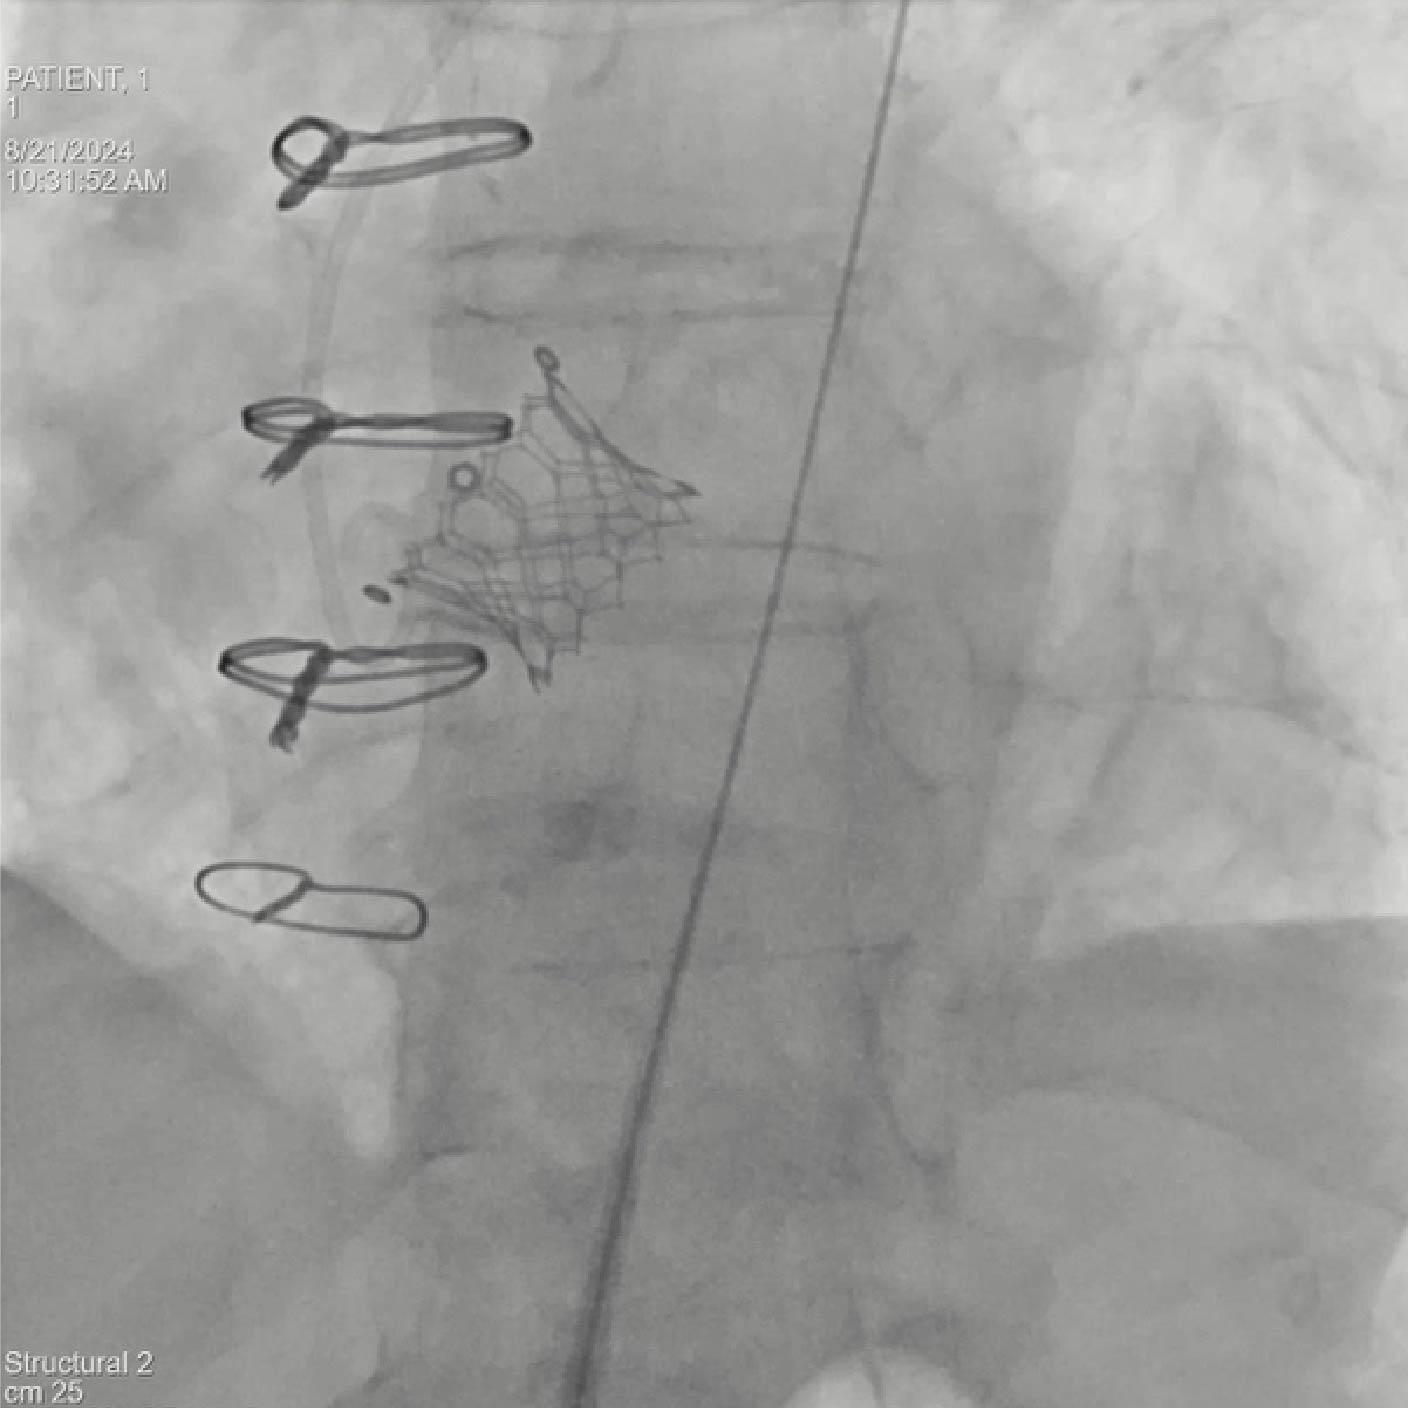

Objetivo clínico: Soporte para la colocación de un dispositivo de protección cerebral como herramienta para mitigar el riesgo de accidente cerebrovascular embólico.

Soluciones y características seleccionadas: ARTIS pheno, Case Flows, Una combinación preestablecida de configuraciones (angulación, disposición de la pantalla, etc.), personalizada para la colocación del dispositivo SENTINEL™*, reduce las interacciones con el sistema. Con Case Flows, una única interacción del usuario reemplaza el ajuste de hasta 6 configuraciones del sistema³. syngo 2D/3D Fusion - Aplicación para superponer la anatomía de la arco aórtico basada en tomografía computarizada sobre fluoroscopia en vivo, para apoyar la navegación del dispositivo. Se ha demostrado que la guía por fusión reduce significativamente el tiempo de despliegue del dispositivo SENTINEL™* y el uso de contraste⁴.